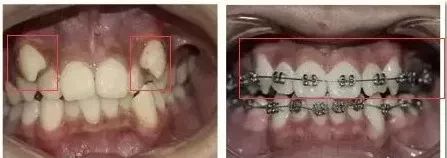

三个月前,小斌来到康贝佳口腔医院,希望医生可以还他一口整齐的牙齿。医生给他制定了金属托槽矫治方案。小斌正式成为牙套族,但让他吃惊的是,三个月后他前来检查牙齿,牙齿已经发生了翻天覆地的变化!

▲

术前X光照

正畸的时间一般在1到2年之间,不过,短短几个月,正畸的效果就可以这么明显!